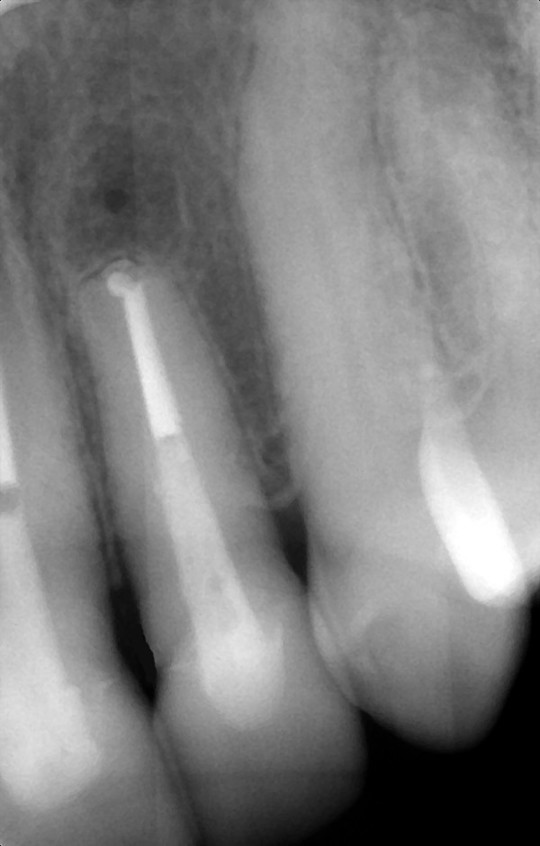

根の先の骨の感染が治らない状態

歯根端切除術・MTA充填直後

術後1年2か月

骨は順調に回復中

根管治療でなかなか根尖病巣が治癒しない、再発を繰り返す、など難治性の根管治療と呼ばれる状態になってしまうことがあります。その場合に、局所麻酔下で外科的に根尖病巣にアプローチして、治す方法があります。

『歯根端切除術』は歯ぐきを剥離して、感染している根尖病巣と根の先端を切除したうえで、根の切断面の根管からMTAという材料を充填する方法です。感染部分を直接きれいにすることができるのに加えて、MTA(アルカリ性の水硬性セメント)の作用で、持続的な殺菌と骨を作る細胞への刺激が期待できます。上手く経過すると、一回の外科処置で、完全に根の先の骨が再生します。

『意図的再植術』は一度歯を抜歯し、感染している根尖病巣と根の先端を清掃し、MTAを充填したうえで、再び歯をもとの位置に戻して固定する方法です。行っていることの本質は『歯根端切除術』と同じです。

二つの方法は状況に応じて使い分けます。まずは徹底した非外科の根管治療を行うことが前提ですが、どうしてもうまくいかない場合に、抜歯の前にこういった方法をとることも可能です。